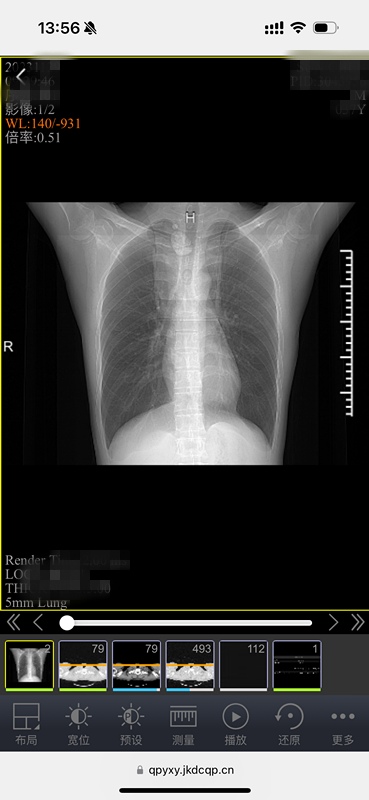

原来,这是中山医院青浦分院为方便百姓就医、优化就诊流程,推出的又一项便民措施——“电子胶片”智慧医疗服务。放射科主任武刚介绍,所谓“电子胶片”,就是患者在中山医院青浦分院做了放射DR、CT、磁共振等检查后,无需再去窗口等待打印传统胶片,用手机、ipad等移动终端扫描报告单上的二维码,检查的影像资料就可以全部在手机上显示,临床医生也可以使用电脑查看影像资料。

电子胶片,不光保存方便,携带方便,医生还能看原始数据。什么叫原始数据?简单地说就是“电子胶片”包含全部图像,支持对图像进行放大缩小、调节明暗等专业操作,能更好地看清病灶,更利于诊断。